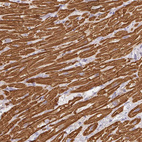

Immunohistochemistry analysis in human heart muscle and skeletal muscle tissues using HPA051884 antibody. Corresponding MYL4 RNA-seq data are presented for the same tissues.